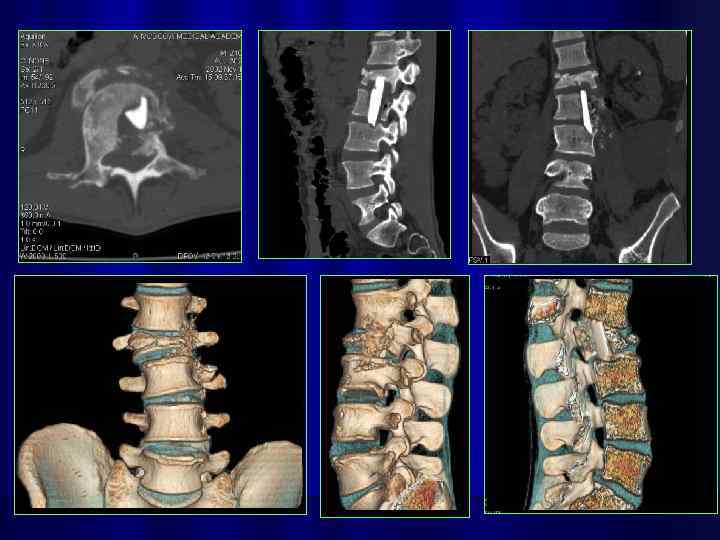

3 -d реконструкция изображений на 64 срезовом спиральном КТ